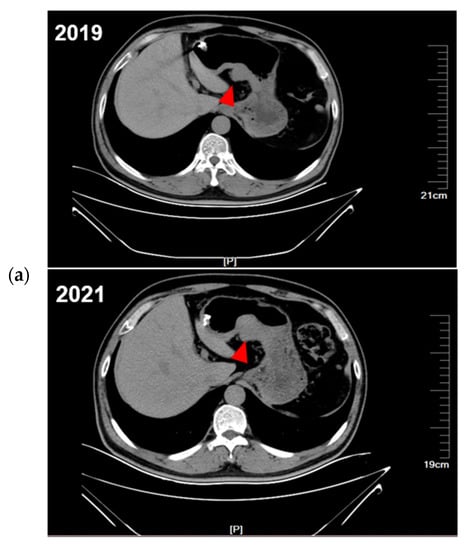

During the follow-up period, the proband was regularly evaluated by CT. Comparing the CT images from 2019, 2021, and 2022 (Figure 2a), the proband was found to have enlarged gastric subepithelial lesions (the largest tumor progressed from 2.5 cm to 3.8 cm in diameter). Other multiple exophytic growing gastric nodules were also found during enlargement by endoscopy. Considering the progression of diffuse gastric lesions, the proband underwent a total gastrectomy in 2022. The gross specimen of the proband showed multiple diffuse extraverted stromal tumors in the entire stomach (Supplementary Figure S2). The proband’s niece also showed progression of the gastric lesions, so ESD was performed. A schematic of the diagnosis and treatment strategy timeline for this family is presented in Figure 2b.

Figure 2.

The diagnostic and therapeutic process of this family. (a) CT showed continued progression of the proband’s GISTs (red arrows). (b) The overall timeline of the entire follow-up process.